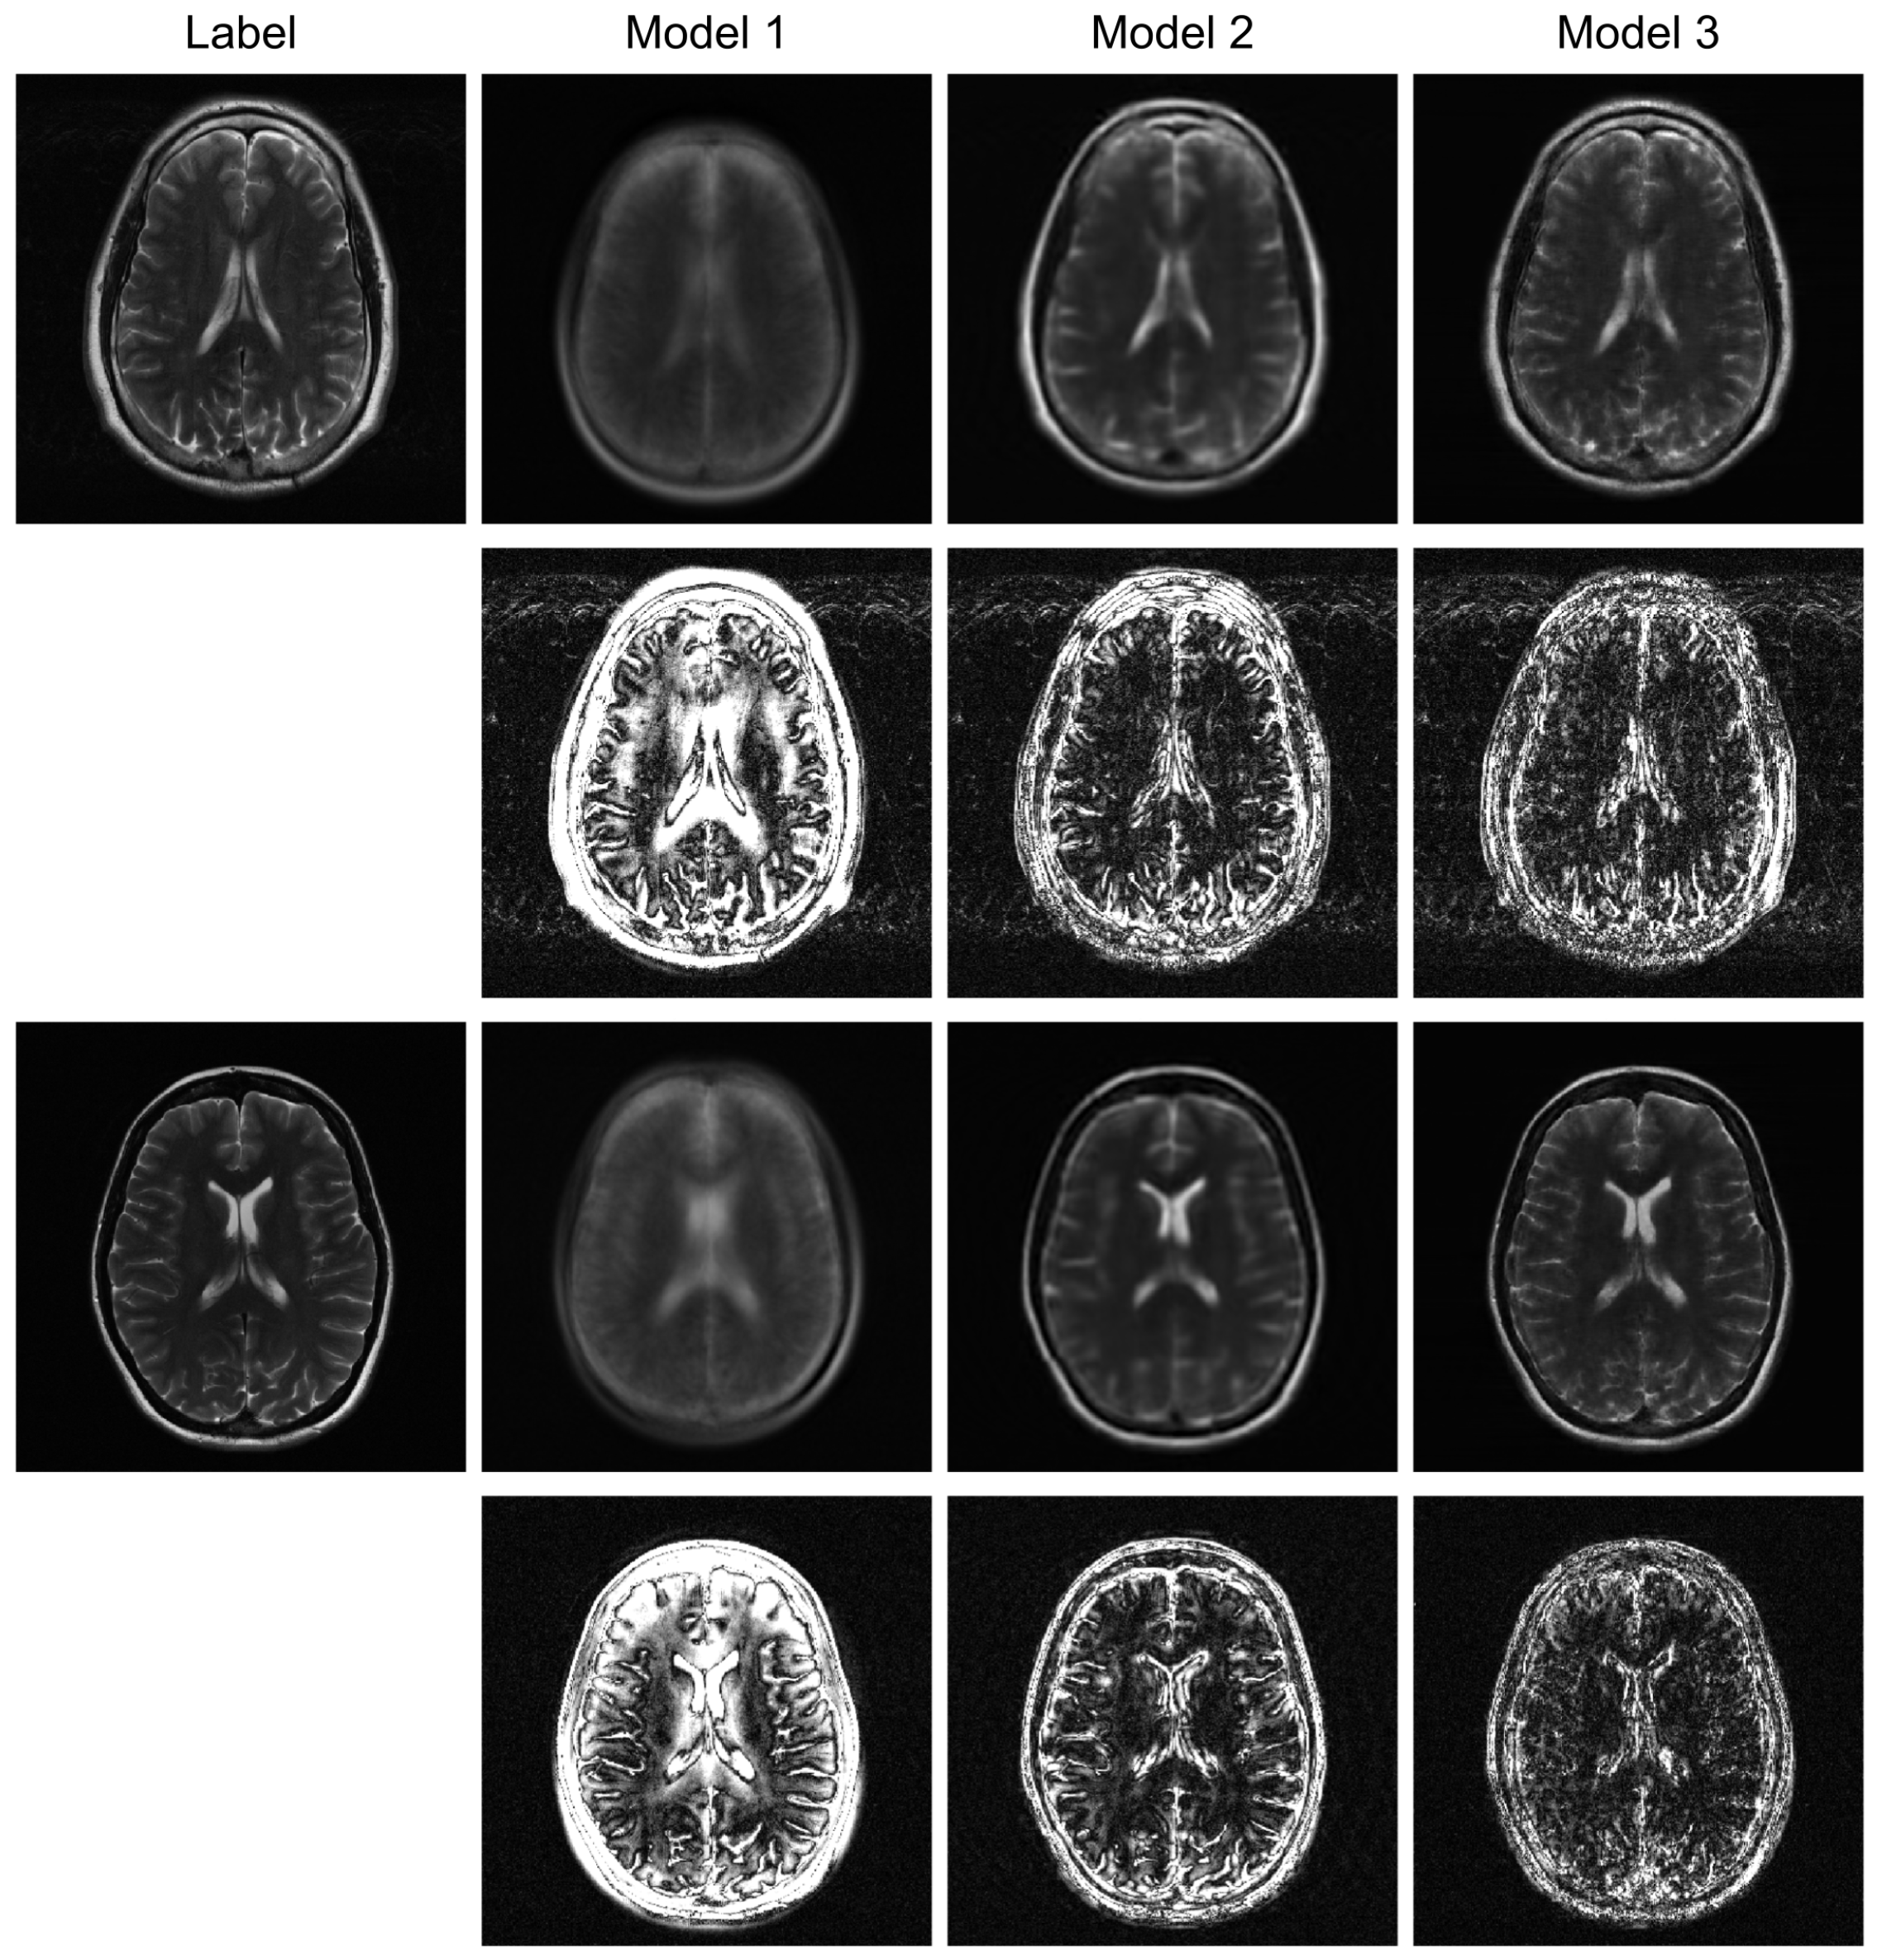

To further evaluate the robustness of our proposed model, we conducted additional experiments under higher acceleration factors (R = 8) and with different undersampling patterns (regular and random). For the random sampling scenarios, a new undersampling mask was randomly generated for each sample, which prevents the model from overfitting to a fixed pattern and enhances generalization. The qualitative results are presented in Figure 3, Figure 4 and Figure 5, and the corresponding quantitative analysis is summarized in Table 1. At a higher acceleration factor of R = 8 (Figure 4 and Figure 5), the performance gap between the models becomes more pronounced. While all models exhibit increased artifacts compared to R = 4, Model 3 consistently preserves anatomical structures more effectively than the other models, particularly in the more challenging random sampling scenario (Figure 5). The quantitative results in Table 1 align with the visual assessment. Across all tested scenarios—R4 random, R8 regular, and R8 random—Model 3 consistently achieves the lowest nMSE and the highest SSIM and VIF scores.

The comparison between Model 2 and Model 3 effectively serves as an ablation study, isolating the contribution of the BiRNN module. The significant performance improvement observed in Model 3, particularly under high acceleration (R = 8) and random sampling conditions (Table 2), underscores the critical role of processing k-space data directly. While the Transformer decoder in Model 2 can reconstruct global structures from the encoder’s latent features, it struggles with the complex, non-local aliasing artifacts inherent in undersampled data. The BiRNN module in Model 3 addresses this by interpreting k-space as sequential data, effectively capturing the structured correlations along the phase-encoding directions. This allows the model to disentangle aliasing patterns from true anatomical features before the final fusion step, resulting in superior artifact suppression and detail preservation, as visually confirmed in Figure 4 and Figure 5.

Furthermore, the model’s robustness against different sampling patterns demonstrates its generalization capabilities. The regular sampling pattern (Figure 5) produces coherent, line-like artifacts, whereas the random pattern (Figure 4 and Figure 6) generates more incoherent, noise-like artifacts. Model 3’s consistent high performance in both scenarios indicates that the hybrid architecture, which processes global image-domain context via the ViT and models frequency-domain sequential dependencies via BiRNNs, achieves high adaptability to varying artifact structures. This adaptability is a significant advantage over methods optimized for only a specific type of artifact texture.

Figure 6. Robustness test under a high-acceleration (R = 8) random sampling condition. The reconstructed images and their error maps (10× amplification) demonstrate performance degradation and artifact patterns in a highly incoherent scenario.